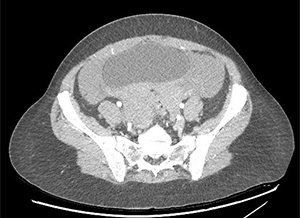

There is a large hemoperitoneum (arrow below) with a massive rectouterine structure (star below) concerning for clot.

We were most concerned about a ruptured ovarian cyst as the patient’s pregnancy test was negative and there was no other obvious cause of blood in the abdomen. She did not have the classic story of onset of pain after intercourse. We did a CT scan because the bedside ultrasound images were difficult to interpret due to the clotted blood. The radiologist suspected ruptured ovarian cyst as the cause of the hemoperitoneum.

This patient developed hypotension in the ED her hemoglobin dropped 2.5 points in 2 hours. She was taken urgently to the OR and had 1 liter of blood removed. She was discharged in stable condition later that day.